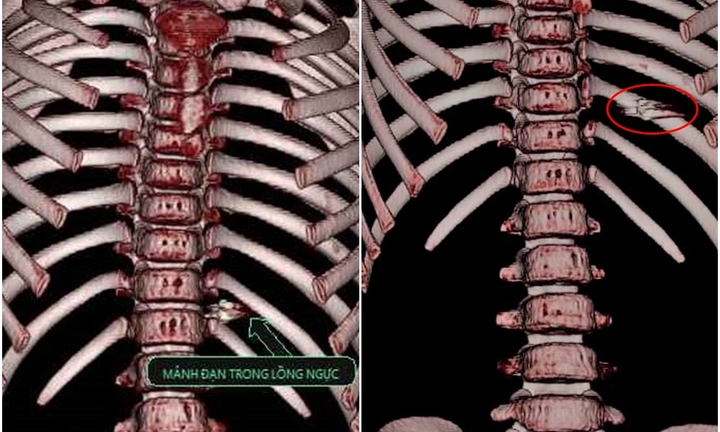

Nạn nhân ngay sau đó được đưa đi cấp cứu tại bệnh viện. Các bác sĩ chụp chiếu, phát hiện một đầu đạn trong cổ. Vết thương của nạn nhân sâu khoảng 1cm, dài 2cm.